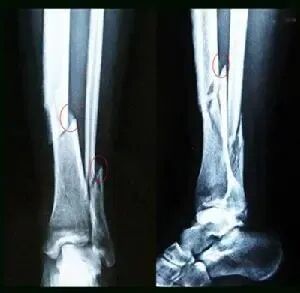

但你知道骨裂是什么吗?骨裂实际上只是一种说法,也是骨折疾病的主要类别之一。在医学上被称为裂纹骨折但它不同于我们常见的骨折没有明显的移位只有一些骨头裂纹属于闭合性骨折

骨裂的一般原因有三类:

首先是直接的暴力损伤。

直接暴力损伤导致撞击部位骨折,连接骨裂部位,往往伴有不同程度的软组织损伤。

二是间接暴力损伤。

在暴力的冲击下,远处的骨骼位置通过传导和杠杆产生骨裂现象。

就像人体从高处坠落一样,当躯干在冲击缓冲中弯曲和伸展时,就会产生骨裂。这是由于挤压导致远离足部的胸椎骨裂骨折。

第三,是累积性的骨头劳损

这通常是指一些骨骼经过多年的反复积压和轻微的直接和间接骨损伤引起的骨裂现象,这通常发生在中老年人身上。

由于中老年人年龄的增长,许多骨密度比成年人更松散,长期工作会对某些关节部位进行过载操作,如步行等。这会对下肢关节施加压力,导致骨裂

与一般性骨折相比,骨裂的危害较轻,因为它不涉及骨移位,治疗相对简单,可以通过传统的石膏或小夹板固定进行治疗。

骨裂患者的恢复速度也比一般骨折患者明显缩短。